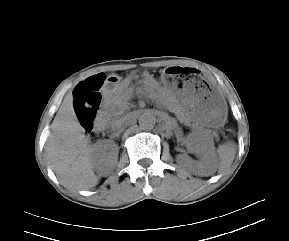

病变位于肝胃间隙,实际就是位于小网膜囊(左肝下后间隙),呈轻度不均匀性强化,腹腔内及腹膜后见多发肿大淋巴结。所以我考虑肝胃间隙恶性胃肠间质瘤并淋巴结转移。

病灶强化不显著,灶周及腹膜后见多量淋巴结肿大,考虑淋巴瘤可能,其次考虑间质瘤

病灶强化不显著,灶周及腹膜后见多量淋巴结肿大,考虑淋巴瘤可能,其次考虑间质瘤。